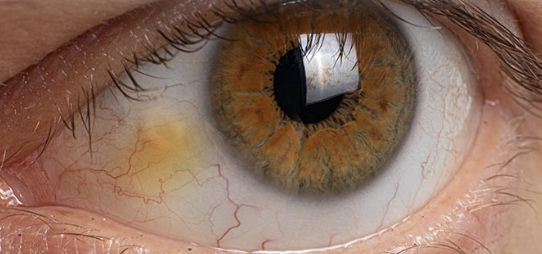

Pinguecula

One of the Normal Findings for 6. Inspect bulbar conjunctiva and sclera

Yellowish nodules on the bulbar conjunctiva

Harmless nodules common in older clients

Appear first on the medial side of the iris and then on the lateral side

Early Pterygium

One of the 6 Corneal Abnormalities

Thickening of the bulbar conjunctiva that extends across the nasal side